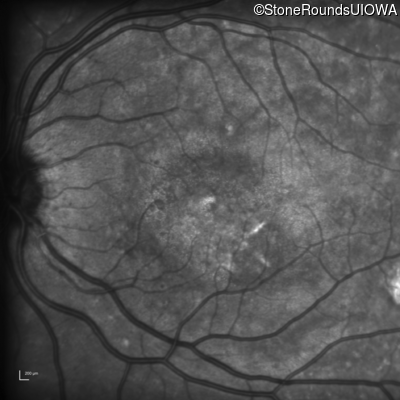

Infrared Fundus Photograph - Right - 20/100 sc

Exemplar